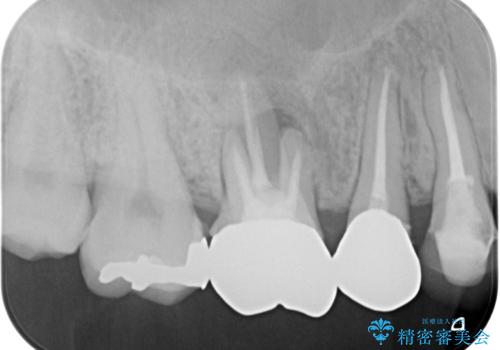

レントゲン等、検査を行ったところ骨の厚みは問題ないですが、

高さは少し低かったので、幅が太い短いインプラントを使って治療を行う計画を立てました。

インプラント治療により問題無く奥歯で噛めるようになりましたが、奥歯の噛み合わせが強いためインプラント周囲の骨吸収や他の歯の破折等が起きる可能性があります。

夜間就寝時のマウスピース装着、定期的なメンテナンスでレントゲン、噛み合わせの確認は必須です。